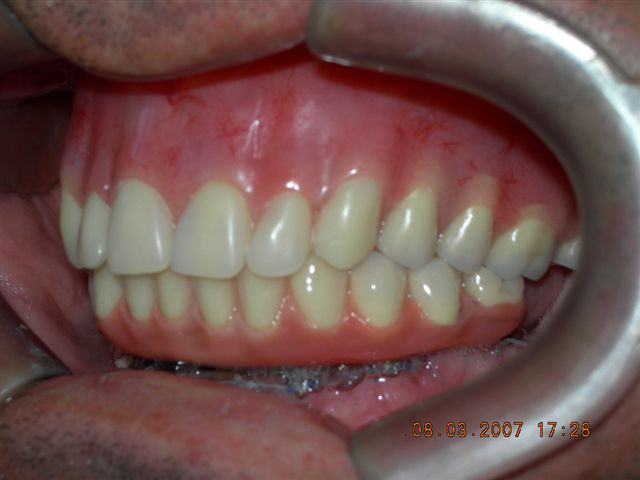

| Próteses antagonistas (VISTA DIREITA) |

Próteses antagonistas (VISTA ESQUERDA) |